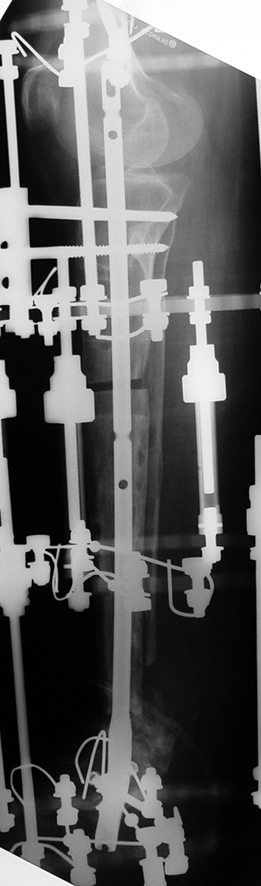

Recently, ilizarov techniques which is basis depend on distraction osteogenesis , bone segment transport or acute shortening after the resection at the site of pseudarthrosis combined with lengthening at another level of bone have been used. These treatment techniques may include some advantage for problems of infection, leg-length discrepancy, soft-tissue loss, and joint contracture.

Case 2